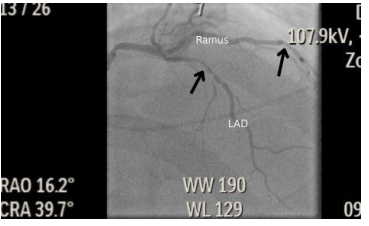

A 64-year-old Caucasian male was admitted to our hospital for a staged angioplasty and stenting procedure after a recent left heart catheterization which revealed a significant 80% stenosis of the proximal left anterior descending artery (LAD) and a significant 90% stenosis of the proximal ramus intermedius (Figure. 1)

Figure 1: RAO cranial view showing significant stenosis (black arrow) to the proximal LAD and R1